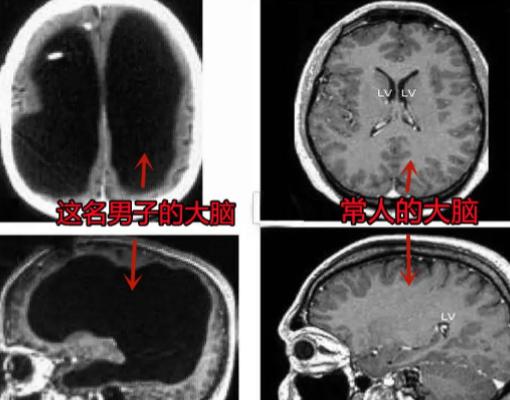

2007年,法国出现了一个“无脑”人!原来一男子在做脑部检查时,竟然被发现他没有大脑,更让人意外的是他的身体却非常健康,后来还考上了公务员,成了两个孩子的爸爸。 2007年,法国一医生被彻底吓傻了:一个44岁的政府公务员,脑壳里竟然全是水。 按医学常理他早该没命了,可他不仅活蹦乱跳,还娶妻生子,处理政务公文比谁都利索。这件事直接震碎了神经科学界的认知,脑子都没了,人怎么还能活得这么好? 当年这位大哥因为左腿有点发软,去里昂大学医院做了个检查。医生本来觉得是小毛病,结果核磁共振影像一出来,办公室瞬间死一般寂静。 他的颅内几乎空无一物,原本肥厚的大脑皮层被积水挤成了一层蝉翼般的薄片,紧紧贴在天灵盖上。 换句话说,他损失了绝大部分的脑组织,剩下的厚度还不如一张大饼。可就在这种“重度伤残”的状态下,他不仅是两个孩子的父亲,还是受人尊敬的国家公职人员。 他日常逻辑清晰,语言表达流畅,在社会坐标里,他是一个完全称职、甚至优秀的公民。 2008年,国际权威医学期刊《柳叶刀》刊登了此案,彻底颠覆了“脑子越大越聪明”的传统思维。 这个奇迹并非神迹,而是大脑在漫长岁月中搞了一场“权力移交”。原来他半岁时患过脑积水,虽然装过引流管,但14岁那年装置被拆除,隐患就此埋下。 在之后的30年里,他颅内的积水以极慢的速度递增,压力几乎是按微米计算的。 如果是突发脑溢血,人肯定当场交代,但这种慢速压迫给了神经系统喘息和自愈的机会。为了活命,他的大脑启动了极端的“代偿机制”,在绝境中开始了功能重组。 科学家推测,在大脑皮层逐渐萎缩的过程中,那些进化史上最古老的区域,比如脑干和基底节,被迫接了班。 这些“老干部”打破了原有的职能边界,重新构建突触连接,硬是接管了高级思维任务。这证明了生命具有惊人的主观能动性,能在废墟上维持住意识的火种。 这起案例不仅是医学界的地震,更像是一场社会学层面的重击。 长期以来,我们习惯用冷冰冰的器械数据去预判一个人的智力,但这大哥直接拆解了这种傲慢。 在医学影像里他是丧失劳动能力的残疾人,但在现实生活中,他却比很多身体健全的人更有价值。 2009年,受此案例直接推动,法国修订了相关的就业与残障认定标准。 法律开始承认:评价一个人的认知水平,不应看他的脑子长成什么样,而应看他为社会贡献了什么。这在制度层面为无数生理上有瑕疵的人,争取到了生而为人、平等工作的尊严。 里昂的这个奇迹至今仍在警示我们:人类对生命潜能的认知还极其肤浅。当大脑皮层萎缩至极限,生命依然能靠着残存的神经纤维,在液体的包围中搭建起智慧的宫殿。 永远不要轻易被生理结构定终生,因为生命本身,就是一种在压力下不断重塑自我的顽强意志。 信源:快资讯《科学尽头是神学?世界首例“无脑人”,娶妻生子还考取公务员!》